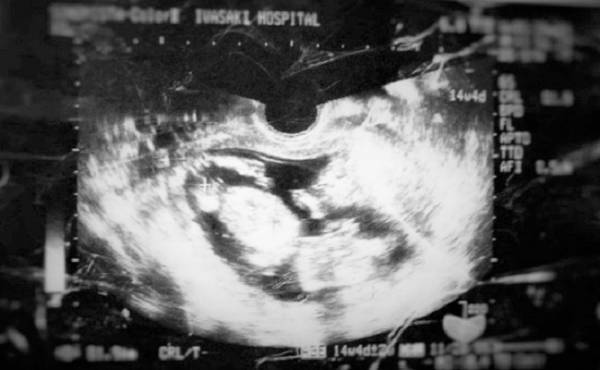

驚きの出生体重!!生まれた赤ちゃんは超ビッグだった!【出産体験談】

第2子である次女の出生体重は、なんと4,268g! 生まれてびっくり!! とてもビッグな赤ちゃんでした。2度目の出産とはいえ、なかなか赤ちゃんが出てこなくて、分娩台の上でいろいろと悪戦苦闘! そのときのエピソードをご紹介したいと思います。

妊娠7カ月のときに微量の前期破水があり、子宮頚管を縛る手術をしていました。手術以降、医師より安静を言い渡されていたため、あまり動けなかったことが災いしてか、おなかの中の赤ちゃんの推定体重は今までにないほど増加の一途をたどりました。